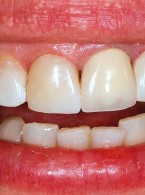

Pokrycie mnogich recesji dziąsłowych

metodą płata przesuniętego dokoronowo z wykorzystaniem przeszczepu podnabłonkowej tkanki łącznej i kolagenowego materiału ksenogennego po wcześniejszej rekonstrukcji połączenia szkliwno-cementowego - opis przypadku